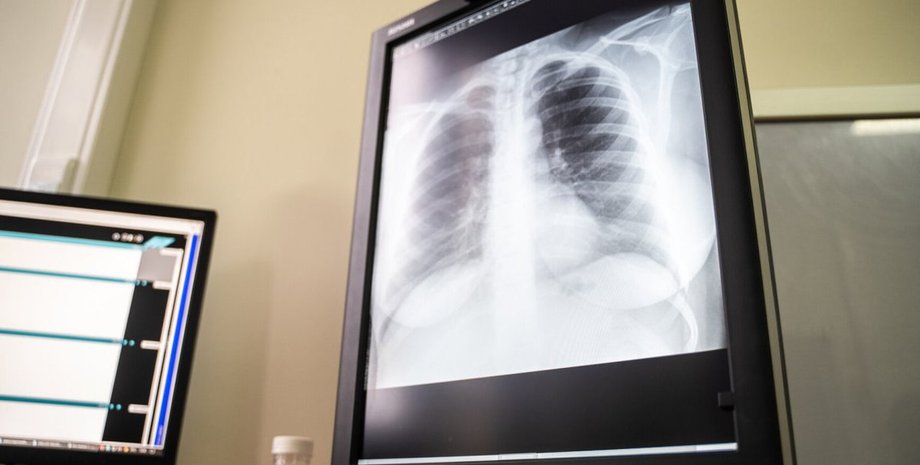

рентген, легкие, коронавирус

Фото: Телеканал 360